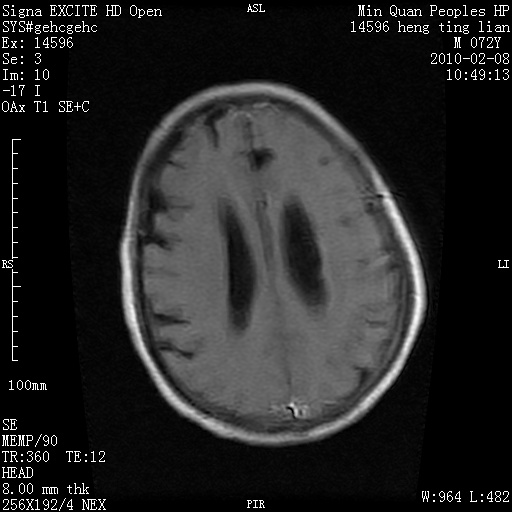

m,72,头疼,头晕两年,伴视力模糊三月,饮食呛咳两天。pe:颈部抵抗,左眼突出,左眼瞳孔约3mm,对光反射消失,双眼失明,伸舌困难,双肺呼吸音粗,心率110次/分,左上肢肌力i级,左下肢屈曲,肌张力高。现有08年2月19mri平扫及10年2月8日mri增强请会诊。ct病灶呈低密度伴散在点、片状等密度区,无明确钙化(无ct片资料可供上传)。[

左侧桥小脑区占位伴梗阻性脑积水----考虑 1神经鞘瘤 2室管膜瘤。

左侧桥小脑区神经鞘瘤伴梗阻性脑积水。

左侧桥脑小脑角区肿瘤并脑积水,考虑听神经瘤,脑膜瘤?

左侧桥脑小脑角区肿瘤并脑积水,考虑听神经瘤,